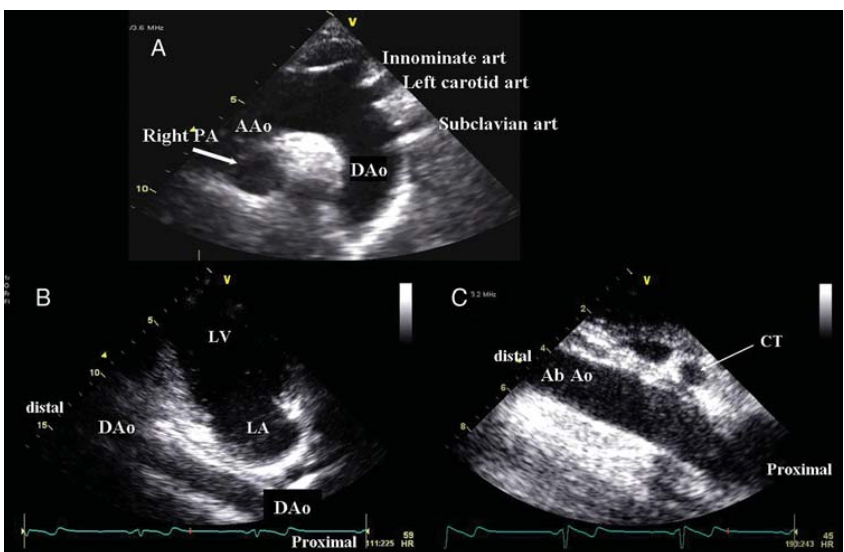

Normal Anatomy

In a normal left-sided aortic arch, the fist branch should be the:

A

innominate artery or brachiocephalic artery4

The branches arising from the aortic arch are the:

• innominate (brachiocephalic) artery

• left common carotid artery

• left subclavian artery